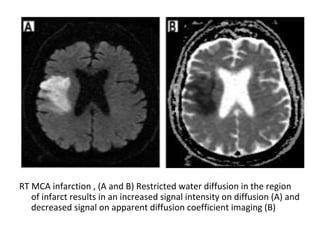

RT MCA infarction , (A and B) Restricted water diffusion in the region

of infarct results in an increased signal intensity on diffusion (A) and

decreased signal on apparent diffusion coefficient imaging (B)